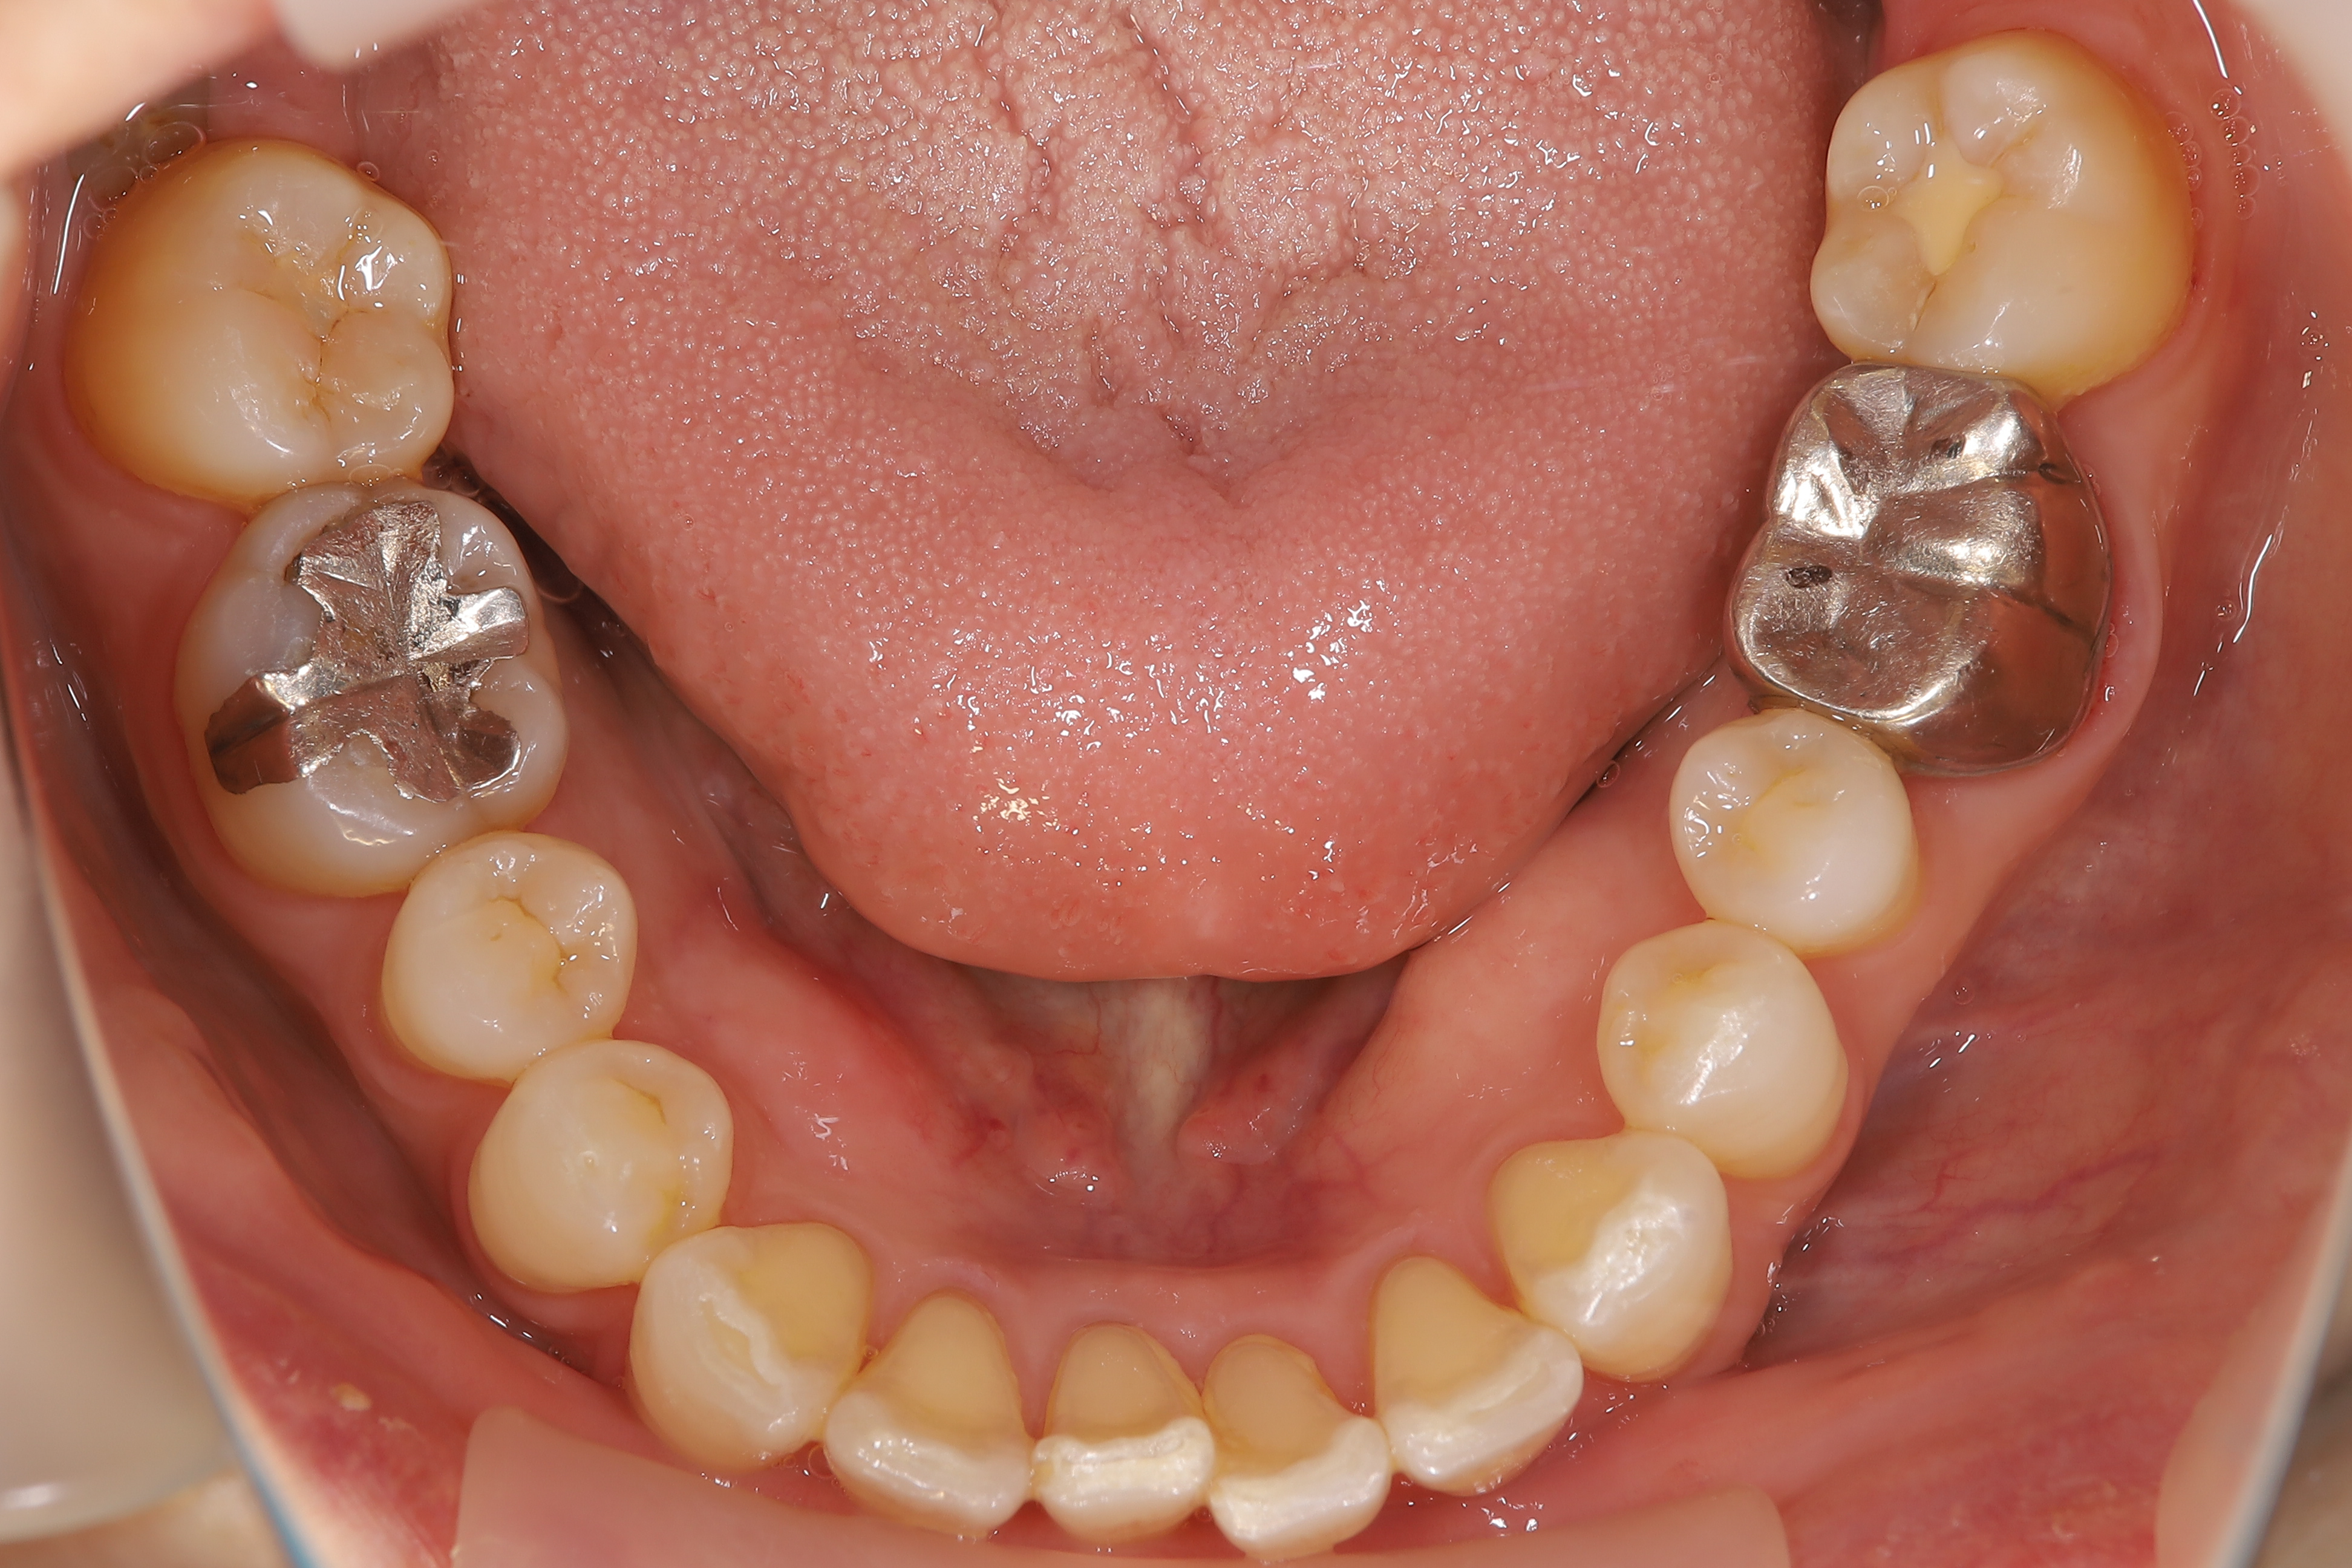

審美歯科治療

症例紹介